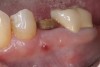

Fig 12. (Case 2) Tooth No. 9 was extracted; the buccal plate was dehisced.

Figure 12